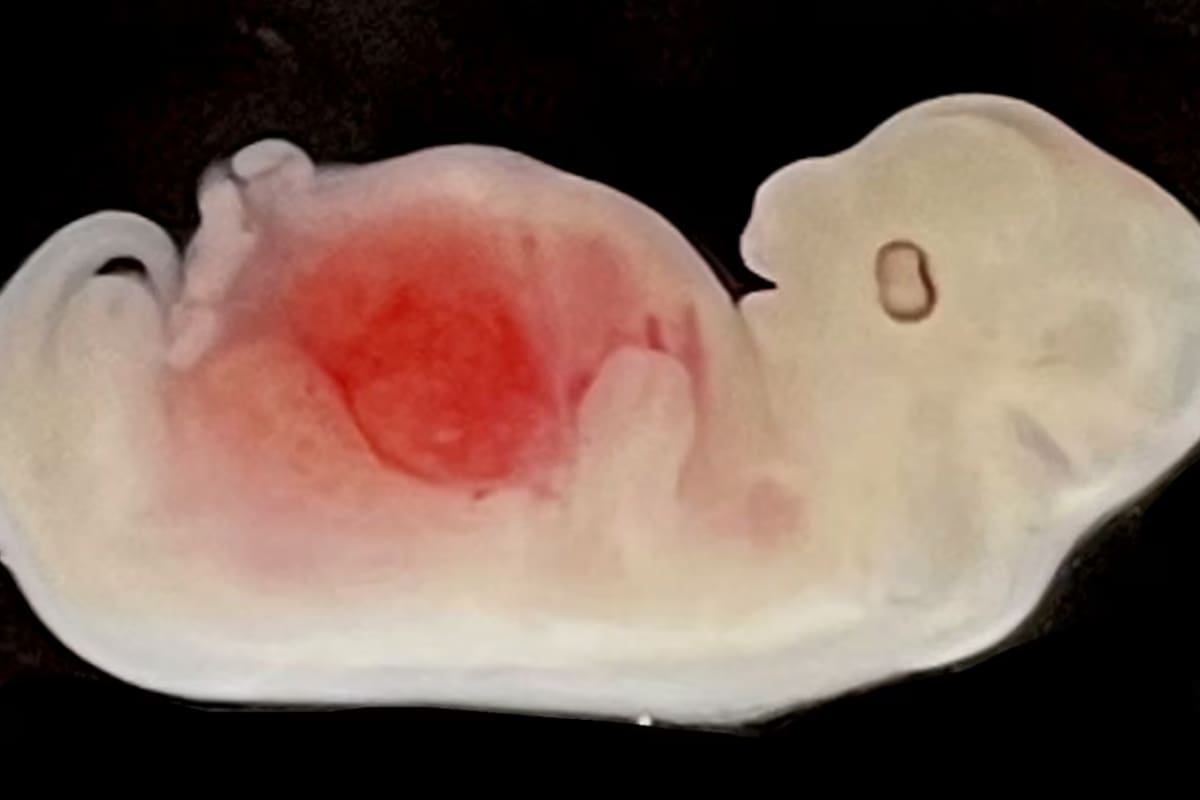

MADRID.– La imagen es histórica. Un equipo de científicos chinos y el médico español Miguel Ángel Esteban lograron por primera vez generar un esbozo de órgano humano en otro animal. El experimento, realizado con riñones humanizados en embriones de cerdo, supone un salto hacia el todavía lejano sueño de utilizar otros mamíferos como fuente inagotable de órganos para trasplantes. Estos organismos híbridos –denominados quimeras por el monstruo mitológico con cabeza de león, vientre de cabra y cola de dragón– suscitan todavía unos monumentales dilemas éticos.

Esteban, nacido hace 53 años en la localidad valenciana de Castellón de la Plana, se mudó a China en 2008. Allí, en el Instituto de Biomedicina y Salud de Guangzhou, el español y sus colegas chinos reprogramaron células humanas adultas hasta recuperar su capacidad de formar cualquier órgano o tejido del cuerpo. El equipo introdujo esas células humanas pluripotentes en embriones de cerdo de pocos días, modificados genéticamente antes para que no desarrollen riñones porcinos. Las células humanas ocuparon ese nicho vacío y generaron un riñón rudimentario, una fase intermedia del sistema renal llamada mesonefros. Estos embriones de cerdo-humano fueron gestados en cerdas hasta los 28 días, aproximadamente una cuarta parte del tiempo de preñez de la especie. La mitad de las células de sus riñones son humanas.

El equipo de Miguel Ángel Esteban y Liangxue Lai trabaja ahora con el objetivo de lograr riñones maduros, intentando sortear los obstáculos técnicos y éticos. Una de las líneas rojas es evitar que las células humanas escapen del riñón y se integren en el cerebro del cerdo o en sus gónadas, ya sean testículos u ovarios. “La cuestión es si es éticamente correcto dejar que nazcan cerdos con riñones humanizados maduros. Todo dependerá del grado de contribución [de las células humanas] en otros tejidos del cerdo”, opina Esteban. Su estudio, publicado hoy en la revista especializada Cell Stem Cell, muestra que “muy pocas” células humanas se dispersaron por el cerebro y la médula espinal de los embriones porcinos. “Para eliminar cualquier tipo de problema ético, estamos modificando más las células humanas, de manera que no puedan, de ningún modo, ir al sistema nervioso central del cerdo”, afirma el médico español.